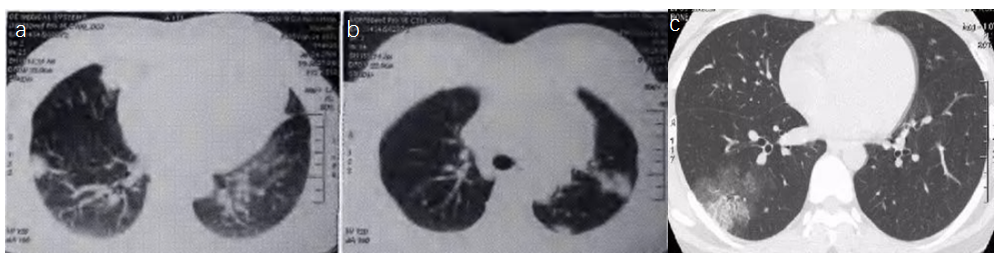

念珠菌感染累及多个系统或脏器成播散性念珠菌病。播散性念珠菌病往往在肺部呈现弥漫分布的斑片大片实变磨玻璃改变(如图1),也可有多发小结节样改变[1]。慢性播散性念珠菌病(CDC)也称为肝脾念珠菌病,是一种侵袭性念珠菌病,其病变主要见于肝脏、脾脏和/或肾脏[2]

图1 CT表现(a斑片; b实变; c磨玻璃)